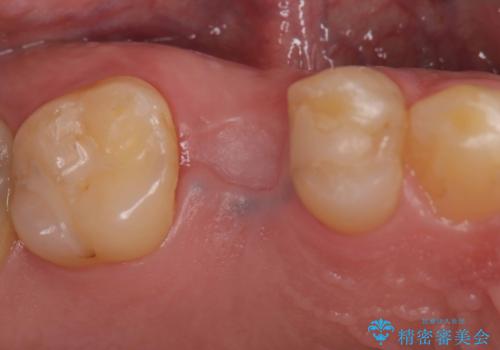

- 「歯茎にニキビみたいのが出来て歯が揺れている」を主訴に来院された患者様です。

右上5番が根尖性歯周炎と歯周病が同時に併発しており、骨が大きく溶け、歯の動揺も著しかったため保存困難と判断をし抜歯してインプラントで治療を行いました。

右上4番は虫歯になっていたので、虫歯を除去後、セラッミクインレーで治療を行いました。